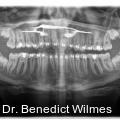

Miniimplantate im anterioren Gaumen werden aufgrund ihrer einfachen Insertion, Vielseitigkeit und der sehr hohen Verlässlichkeit immer beliebter. Der anteriore Gaumen ist aufgrund seiner guten Knochendichte und der meist geringen Mukosadicke ein sicherer Insertionsort, da zudem auch das Risiko einer Wurzelverletzung minimal ist. Fotos: © Prof. Dr. Benedict Wilmes